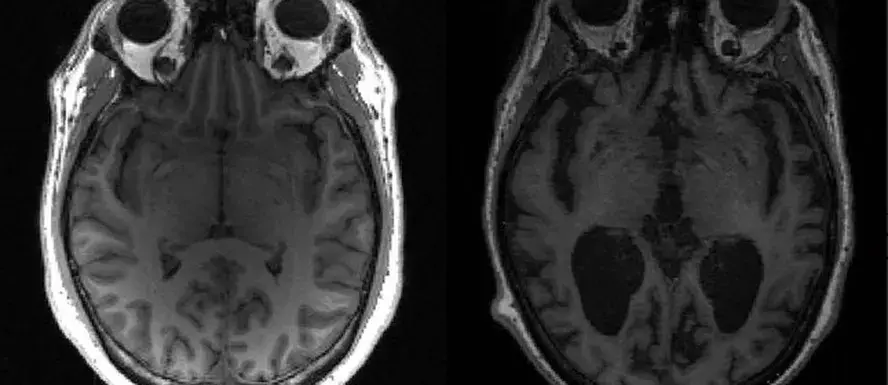

O Fleury afirmou que o teste atingiu precisão de 88% quando comparado aos resultados quantitativos do PET amiloide cerebral. “É um exame de equivalência, mas ainda não faz parte dos critérios diagnósticos”, disse Dutra, neurologista do Fleury. “Ou seja, possivelmente será utilizado para complementar (outros exames) e, com a progressão da confiança, pode ser que futuramente ele faça parte de um dos critérios diagnósticos para doença de Alzheimer”, completou.